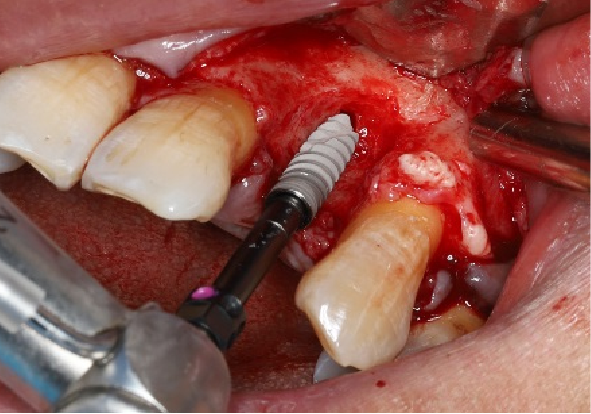

五、标准种植外科备洞程序

使用球钻定位,逐级备孔。

完成备洞。

旋入种植体,初期稳定性为 30N。

直接上愈合基台。

六、GBR程序

术前抽静脉血制备的PRF胶原膜。

PRF浸出物调拌同种异体骨修复材料(拜欧金)。

颊侧缺损处放置骨修复材料,超出骨缺损区3-5mm,并将骨修复材料用力压实。

使用猪小肠粘膜下层来源的可吸收生物膜(瑞拜欧)覆盖骨修复材料表面。

修剪生物膜将其覆盖于植骨区(大小超出植骨区3-5mm),由于瑞拜欧可吸收生物膜具有良好的亲水性能和延展弹性,可完全自然舒展贴合植骨区,本例未做辅助固定,瑞拜欧生物膜表面PRF膜交叉覆盖。